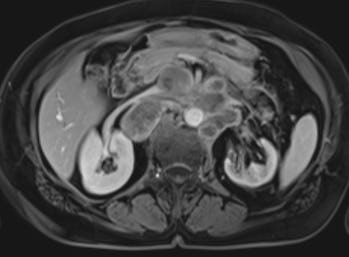

والنتيجة: لم يكن OrganEx قادرًا فقط على تدوير الأكسجين والدم وعكس الموت، بل نجح في إبقاء الأنسجة في الأعضاء في القلب والرئتين والكبد والكلى والبنكرياس سليمة، وأظهرت الخلايا أنها نشطة التمثيل الغذائي.